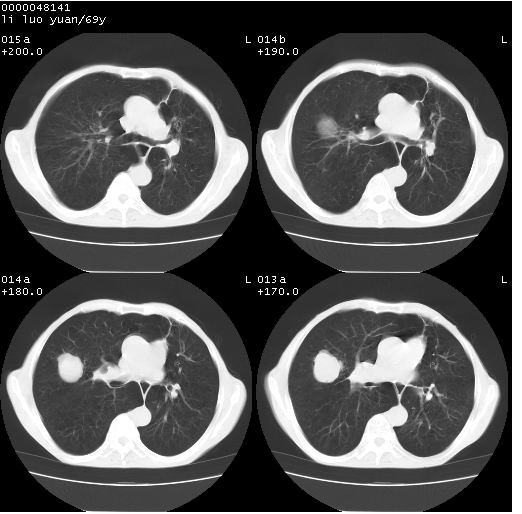

临床资料:老年患者,咯血、消瘦

影像表现:桶状胸,双肺纹理纤细、紊乱,透过度增高,肺野内可见多发、散在、大小不等的无壁高透过影,右肺中叶外侧段分叶样软组织占位,左上肺纤维索条样密度影,相应层面左侧胸腔轻度萎陷,纵隔左移。

影像诊断:1、慢支、肺气肿、双下肺野肺大泡形成

2、左上肺陈旧性肺结核

3、右肺中叶外侧段占位 考虑肺ca可能性较大、建议增强及痰检脱落细胞